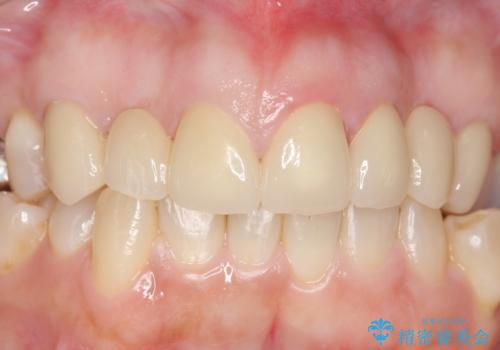

- 昔治療した前歯の被せ物の見た目を改善したいといらっしゃった方の症例です。

左上4番目の歯から右上3番目の歯まで計7歯のクラウンを除去し、オールセラミッククラウンによる補綴を行いました。

今回用いたオールセラミッククラウンはジルコニアフレームという白い素材の上にセラミックを盛っているため、審美性が非常に高いのが特徴です。

また、ジルコニアは人工ダイヤモンドの材料にも使われているほど高い強度を持っており、そのためオールセラミッククラウンは審美性だけでなく、奥歯やブリッジの補綴も可能とするクラウンです。